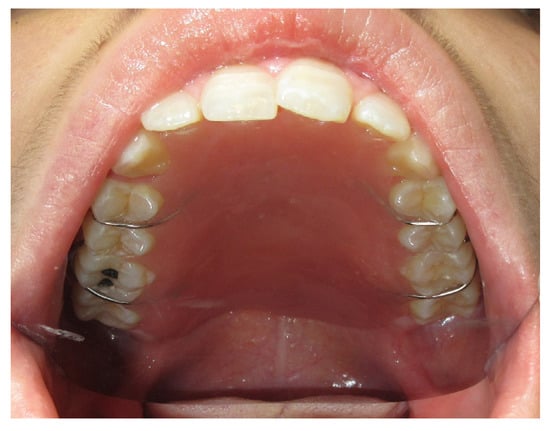

3.1.1. Case 1: A.R.

| A.R | X | * | 5 | 1 | ||